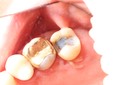

Mark Chun #18 pre-op

Mark Chun #19 caries removal

Mark Chun #18 prep

Mark Chun #18 finish